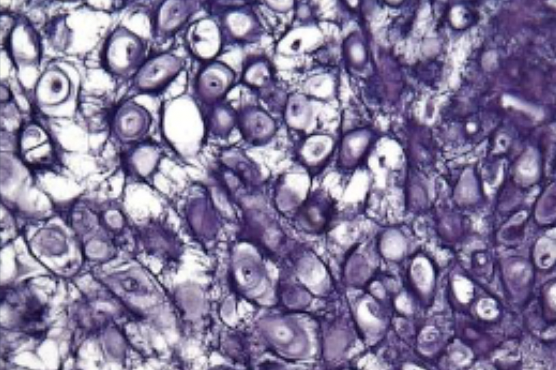

what is this

hyaline cartilage